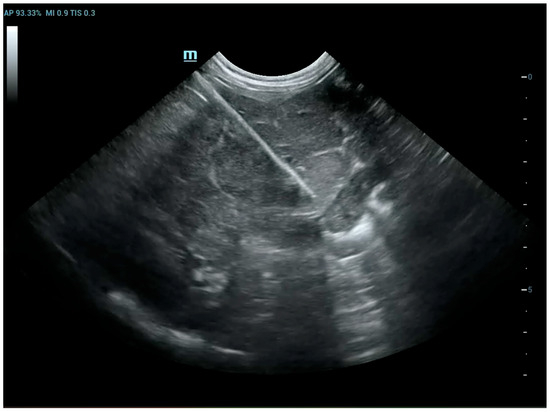

The Usefulness of Extemporaneous Cytological Examination in Imaging-Guided Biopsies

by Andrea Rubini, Francesca Del Signore, Massimo Vignoli, Arianna Miglio, Martina Rosto, Andrea De Bonis, Rossella Terragni, Domenico Santori and Morena Di Tommaso

This study investigates the usefulness of extemporaneous cytological examination performed during imaging-guided biopsies in dogs and cats. In veterinary diagnostics, imaging techniques such as ultrasound and computed tomography are essential for identifying lesions, but they cannot distinguish between inflammatory and neoplastic processes. Biopsies [...] Read more.

This study investigates the usefulness of extemporaneous cytological examination performed during imaging-guided biopsies in dogs and cats. In veterinary diagnostics, imaging techniques such as ultrasound and computed tomography are essential for identifying lesions, but they cannot distinguish between inflammatory and neoplastic processes. Biopsies are therefore required, and this study explores whether immediate cytological evaluation of tissue cores, rolled onto slides and examined under a microscope, can help determine sample adequacy and reduce the number of biopsies needed. Seventy-nine animals with soft tissue or bone masses underwent ultrasound or CT-guided biopsies, followed by extemporaneous cytology and histopathological analysis. Cellular material representative of the lesion was identified in 81.1% of cases, allowing clinicians to conclude the procedure without further sampling. The diagnostic accuracy of cytology compared to histology was 68.3%, with particularly high accuracy for lipomas, melanomas, and mast cell tumors. When excluding non-diagnostic samples due to poor preparation or lesion characteristics, the accuracy reaches 92.1%. These findings suggest that extemporaneous cytology is a useful tool for verifying sample adequacy in real time, potentially reducing procedural risks and improving diagnostic efficiency. While histology remains the gold standard, this method offers immediate feedback and may enhance clinical decision-making in veterinary interventional diagnostics. Full article